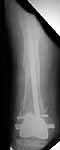

Well, finally i still performed antegrade nailing. After the distractor was applied, reduction of the recent fracture was obtained "automagically".

But the previous fracture resulted with some posterior displacment of the distal part, so antegrade nail would pass anteriorly, and retrograde nail, even a short one, would have penetrated anterior cortex proximally to the fracture. So perQ osteotomy was necessary to add some mobility at the level, and after that the nail was easily inserted to the distal fragment. The nail is solid, 13 mm, locking screws 6 mm. Locked statically.

The radiographs look excellent and a good outcome would be anticipated. The idea to osteotomize the femur shaft to compensate for the prior shaft malunion was clever and should work fine. I can't actually see the osteotomy on either radiograph. Is it more proximal than we see in these radiographsor so well aligned as to be not visible? Have you tried retrograde femoral nailing? Most people find it technically easier although not necessarily better than antegrade.

The osteotomy was performed through the fracture site. See the attachment.